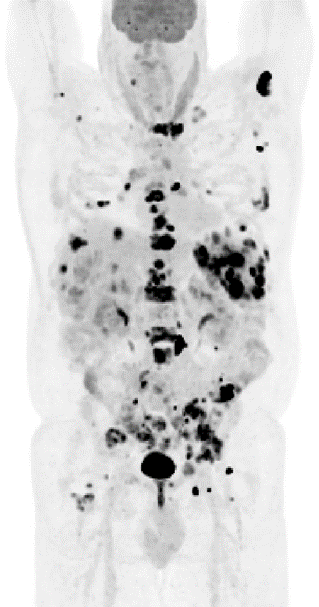

a)

b)

In Fig. 8 we show convergence, via the objective function value as a function of iteration for non-TOF/TOF data, for an 18F-FDG whole-body PET clinical patient (shown in Fig. 7a). This data was obtained from 8 bed positions acquired on a GE D710 PET/CT. The nominal administered activity and post-administration acquisition were 444 MBq and 1-hour, respectively, with 3-minute dwell times and 25% overlap, resulting in total counts, where the bolded numbers are from the bed positions 4 and 6 shown in Fig. 8.